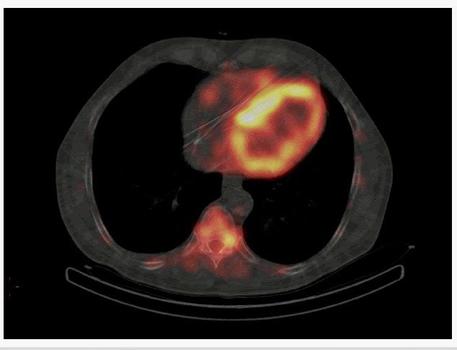

В госпитале имени А. А. Вишневского внедрили в широкую практику новый вид диагностики амилоидоза сердца — сцинтиграфию. Это высокочувствительный неинвазивный метод диагностики заболевания, который ранее делали только военнослужащим.